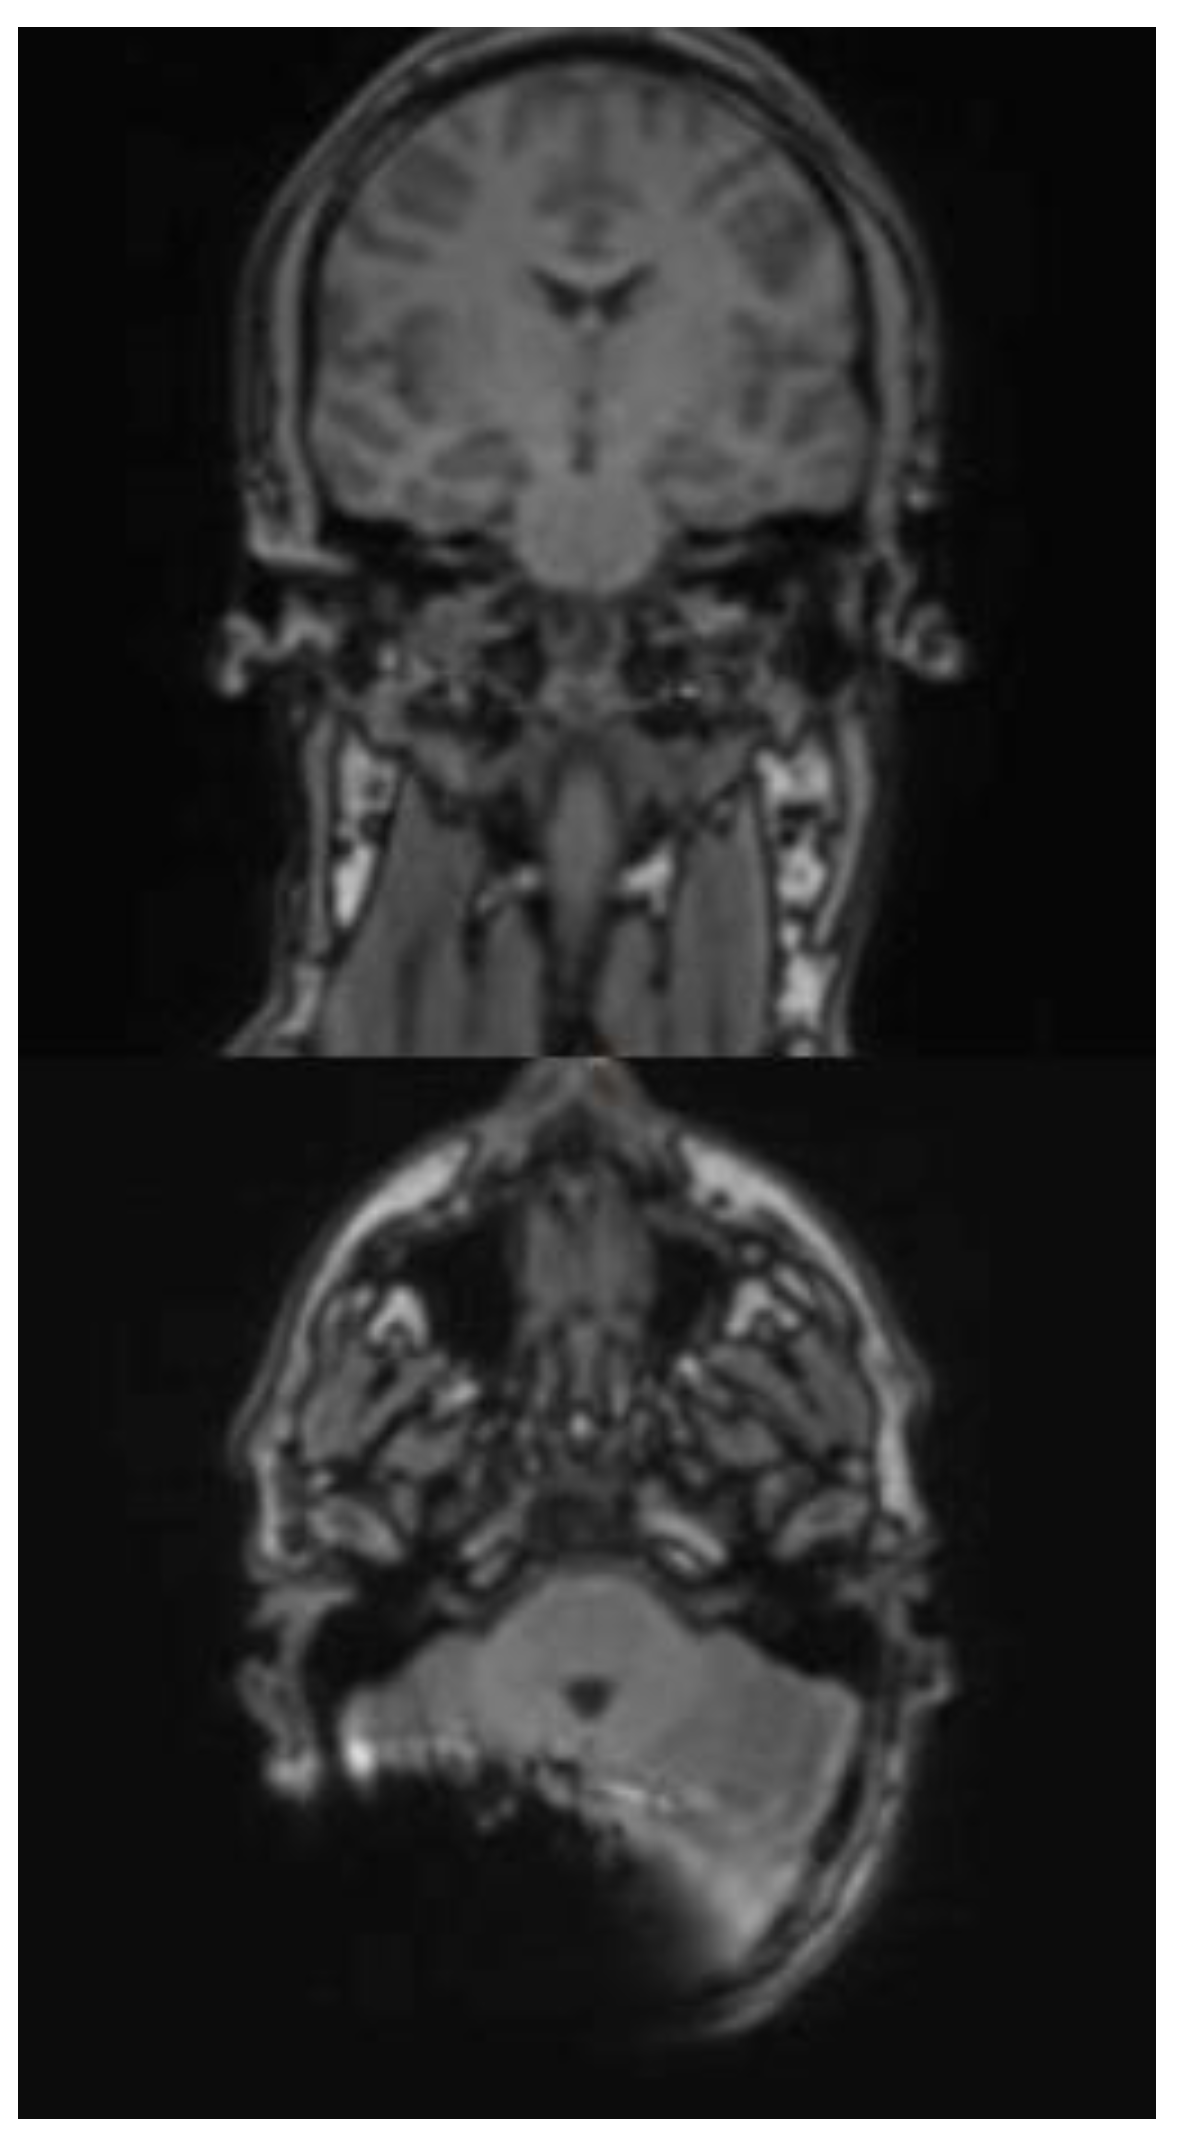

In the HASTE sequence (1.5 Tesla), all three subjects exhibited a signal extinction localized around the cochlear implant, consistent with a metal-induced susceptibility artifact. This is localized ipsilaterally, temporoparietally, and occipitally, and manifests as a centrally hypointense area. The mean extent of the artifact in axial orientation is 60 mm (subject 3: 61 mm; subject 4: 48 mm; subject 5: 71 mm). In the coronal plane, the average extension is 102 mm (test subject 3: 128 mm; test subject 4: 125 mm; test subject 5: 54 mm). In cases 3 and 4, the artifact extension in the coronal plane extends beyond the midline. A relevant geometric distortion of the surrounding structures is not recognizable in any of the cases. Minor, unspecific signal inhomogeneities can be seen at the edges of the artifact zones. Due to the image quality, the anatomical detail recognizability is limited in all three subjects.

In subjects 3, 4 and 5 both the ipsilateral and the contralateral mastoid can be displayed completely and without artifact overlay. The same applies to the internal and external auditory canals, which are imaged artifact-free on both sides. (Figure 4a and b)

The effect of a closer position of the implant to the EAC and a non-anteverted head position inside the scanner is shown in Figure 5a and b. Here, the ipsilateral mastoid and internal auditory canal (IAC) are not assessable.

Figure 4. a and b. Exemplaric scan with HASTE sequence 1.5 T in a coronal and axial plane.

Figure 5. a and b. Exemplaric scan with HASTE sequence 1.5 T in a coronal and axial plane with an EAC distance of 7 cm, without a chin-to-chest position of the head in the scanner.